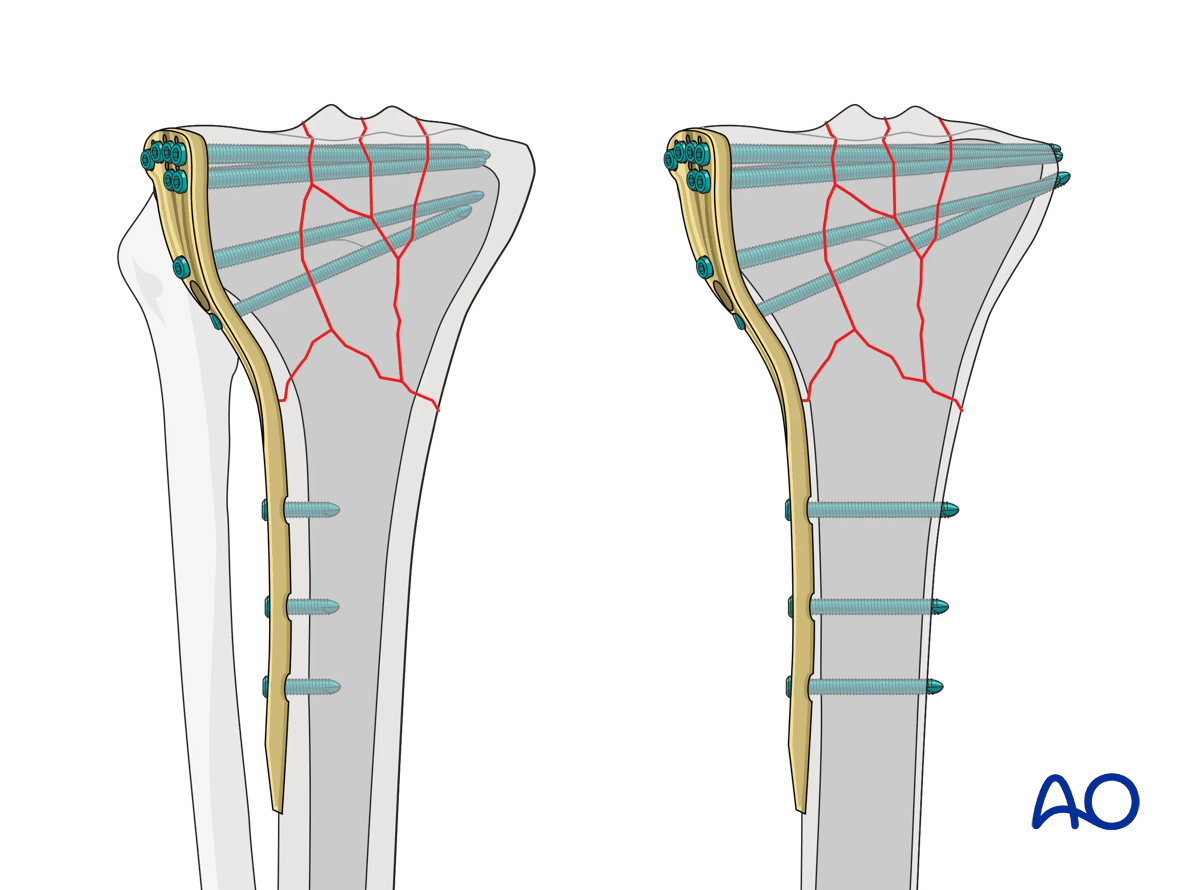

Plate length

When using a bridge-plating technique, which assumes that there is comminution that will be indirectly reduced, the plate length should be approximately three times the length of the zone of comminution, balanced on either side of the fracture area. In the vast majority of instances, however, the comminution is located in the proximal portion of the tibia. Therefore, a general concept is that the distal portion of the plate at least equals the length of the zone of comminution, preferably ending at least at the junction of the middle and distal third of the tibia, with a minimum of 2-3 screws. The screw density in this distal segment should approximate 2.5 screws.

Proximally, given the fact that we cannot take advantage of plate length because of the proximity to the articular surface, the screw density should be increased maximally.

A preoperative x-ray planning template is useful in determining the length of the plate and the position of the screws.

Screw type

In cases of healthy bone structure, unicortical angle-stable screws seem to provide clinically satisfactory stability when cortical bone is normal. However, with significant osteoporosis the torsional and angular stability of the unicortical screw is compromised, as there is a short working length of the screw in the bone. Placement of bicortical screws increases the torsional and angular stability substantially, regardless of the density of the cortex in all situations.